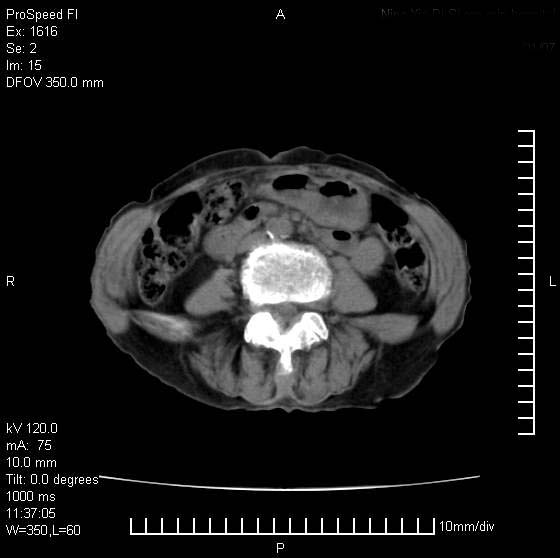

患者无明显临床症状,肝左叶发现一个圆形密度不均的低密度灶,边界较清楚,大小37x45mm,ct值35-70,患者犹豫做增强,如有增强片,我再发上,现先请各位老师会诊.

左肝外叶可见较大圆形低密度影,病灶可见较光整清晰边界,病灶内可见多量条状稍高密度影,右肝前叶亦可见圆形结节状低密度影,边界清晰,密度均匀,考虑1肝多发囊肿,左肝囊肿内出血2肝包虫病3左巨块型肝癌出血合并右肝转移或合并右肝囊肿

左肝外叶可见较大圆形低密度影,病灶可见较光整清晰边界,病灶内可见多量条状稍高密度影

考虑:肝包虫病

肝左叶类圆形低密度影,内可见略高密度影,边界清晰周边可见环形低密度带,考虑肝腺瘤可能,建议增强扫描除外肝血管瘤与肝癌

肝左叶不均匀占位,内有斑片状高密度出血灶,内侧缘似有假包膜,腹主动脉周围及肝门区结构紊乱,似有增大淋巴结,考虑:肝左叶hcc并淋巴结转移。建议增强扫描除外其他。